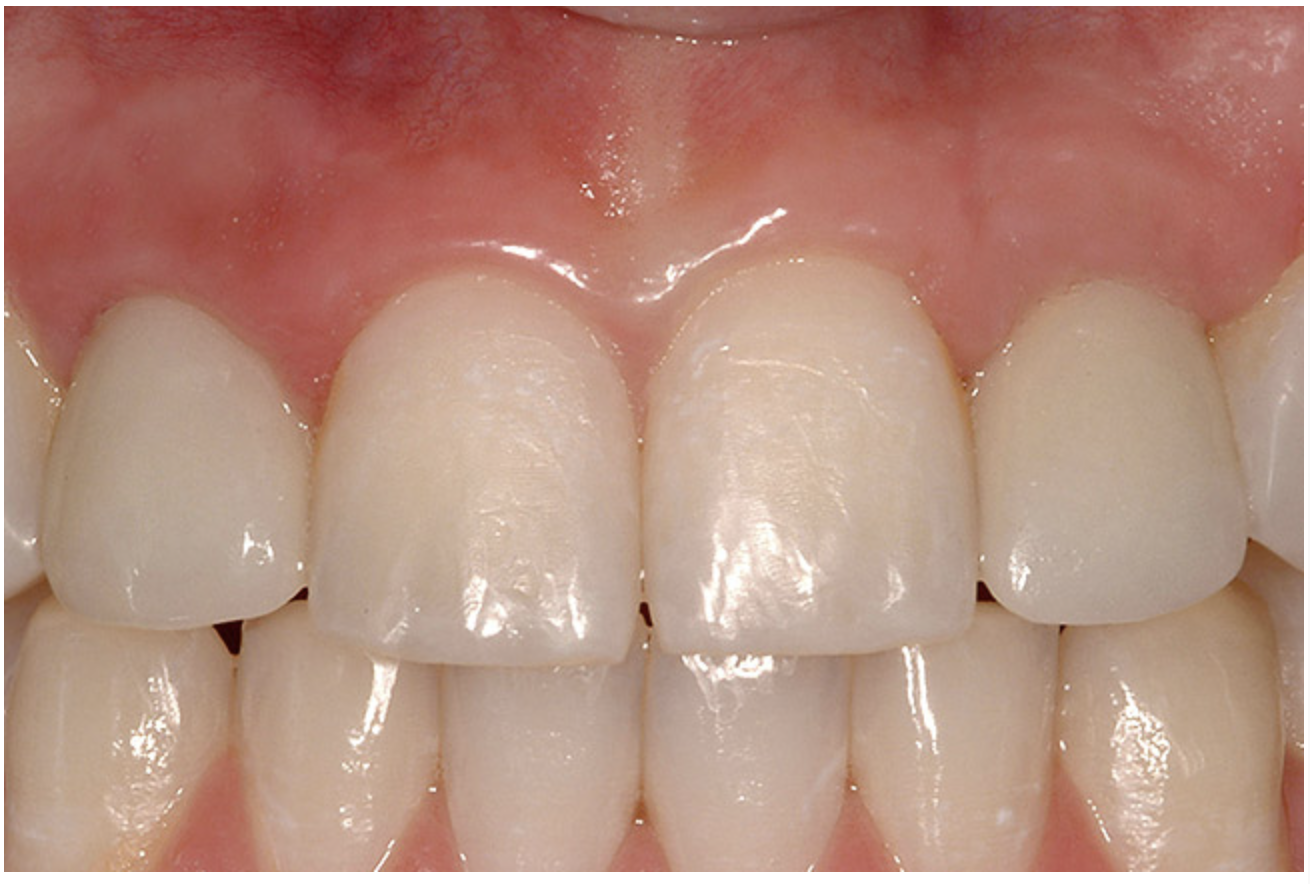

The transitional titanium abutments were left in place for 8 weeks. During this time, the morphologically shaped, computer-milled abutments supported the interproximal tissue and developed the desired emergence profiles. The computer-milled abutments were created to accommodate the adjacent teeth and opposing occlusion, and to aid in the fabrication of the final porcelain-fused-to-metal (PFM) restorations (Figure 20A and Figure 20B). The final crowns were delivered 4 months after implant placement. The radiograph of the emergence profile confirmed the seamless fit of the abutment-implant-crown interfaces (Figure 21). The final restorations were esthetic, functional, and met the needs of the patient (Figure 22A). The re-establishment of the interdental papilla completed the careful transformation of the flat alveolar crestal tissue into a proper emergence of the clinical PFM crowns, indistinguishable from the surrounding dentition (Figure 22B).

Figure 22a  The final restorations are indistinguishable from the surrounding dentition, demonstrating good emergence and re-creation of the interdental papillae.

Figure 22a

Figure 22b  The final restorations are indistinguishable from the surrounding dentition, demonstrating good emergence and re-creation of the interdental papillae.

Figure 22b